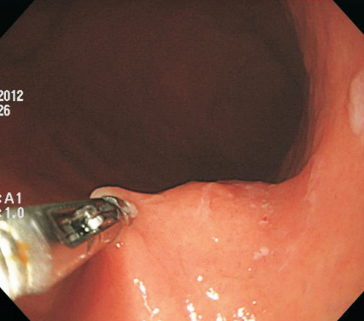

Como fazer?

Primeiramente, é importante ressaltar os materiais necessários para o procedimento. Necessita-se de um gastroscópio convencional com cap, afinal o uso desse dispositivo permite visualização minuciosa da mucosa e do sítio manipulado por acumular menos resíduos na lente do endoscópio.

Uma faca eletrocirúrgica endoscópica é necessária, sendo sugerido o uso de Needle Knife, pois consiste no instrumento de maior poder de corte e menor poder de coagulação, uma vez que se objetiva realizar incisão precisa da mucosa seguida de divulsão dos tecidos. Um princípio básico relacionado às facas endoscópicas consiste no fato de quanto menor a área de contato do instrumento com a mucosa, maior será o poder de corte e menor será o poder de coagulação (figura 1). Sugere-se utilizar unidade eletrocirúrgica com corte em modo endocut, efeito 3 e 40 W.

Outros materiais necessários consistem em pinça de biópsia para divulsão dos tecidos e aquisição de material, assim como clipes metálicos para fechamento do sítio manipulado pós-procedimento. Caso haja necessidade de controle hemostático peri-procedimento, sugerimos o uso de pinça hemostática coagrasper.

O vídeo 1 e as figuras de 2 a 7 demonstram as etapas do procedimento.

Figura 2 a 7. Etapas da biópsia assistida por incisão de mucosa. Fig. 2. Localização da lesão utilizando gastroscópio convencional com cap.Fig. 3 e 4. Incisão na região central da lesão sob auxílio de needle-knife.Fig. 3 e 4. Incisão na região central da lesão sob auxílio de needle-knife.Fig. 5. Divulsão das camadas com pinça de biópsia.Fig. 6. Exposição da submucosa e da cápsula da lesão (seta verde).Fig. 21. Biópsias da lesão sob visão direta. Nota: Posteriormente, realizou-se incisão da cápsula da lesão para biópsia adicionais e, ao término, colocação de clipes para o fechamento do sítio manipulado. Fonte: arquivos do Instituto do Câncer do Estado de São Paulo (ICESP/HCFMUSP).